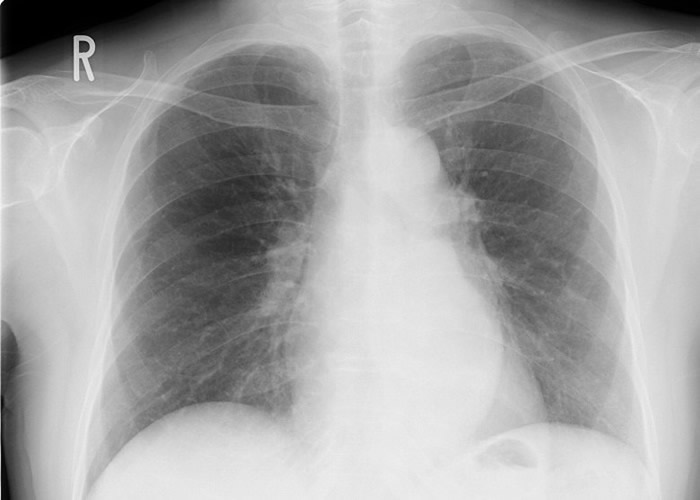

肺癌在多国都是癌症头号杀手。

(蜘蛛网eeook.com报道)据东网:肺癌在多国都是癌症头号杀手,切除手术能有效治愈,但准确找出肉眼看不见的微细病处并非易事。日本京都大学的研究团队周二(15日)公布,研发出可以锁定患处的微晶片装置,以尽量减少损害肺部,这项划时代发明将有助治疗癌症。

肺肿瘤切除手术以往透过电脑断层扫描(CT)确认癌变部位,医生为免扩散,会大范围切除以防复发。新技术先将直径1.8毫米的圆筒形晶片植入患处旁,再开胸插入棒状天线,天线和晶片接近时会共鸣发声,医生便能透过提示声响及胸腔镜确认患处。